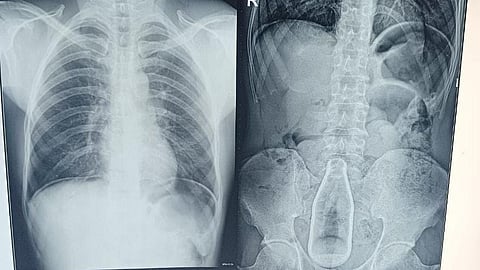

புதுக்கோட்டை மாவட்டத்தைச் சேர்ந்த 45 வயதுடைய ஒரு நபரின் வயிற்றில் குளிர்பானத்தின் கண்ணாடி பாட்டில் இருந்த சம்பவம் அதிர்சியை ஏற்படுத்தி உள்ளது. கடந்த மூன்று நாட்களுக்கு முன்பு அந்த நபர் புதுக்கோட்டை அரசு மருத்துவக் கல்லூரி மருத்துவமனையில் உடல்நலக்குறைவால் அனுமதிக்கப்பட்ட நிலையில், மருத்துவ குழுவினர் நீண்ட போராட்டத்திற்கு பின் அறுவை சிகிச்சை செய்து அந்த பாட்டிலை அப்புறப்படுத்தியுள்ளனர்.

தற்போது அவர் புதுக்கோட்டை அரசு மருத்துவக் கல்லூரி மருத்துவமனையில் சிகிச்சை பெற்று வரும் சூழலில் அவர் வயிற்றுக்குள் எவ்வாறு 7up பாட்டில் போனது என்பது குறித்து விசாரணை மேற்கொண்டு வருகின்றனர். ஆசனவாயில் வழியாகவே பாட்டில் உள்ளே நுழைந்திருக்க வாய்ப்புள்ளதாக கருதப்படுகிறது.